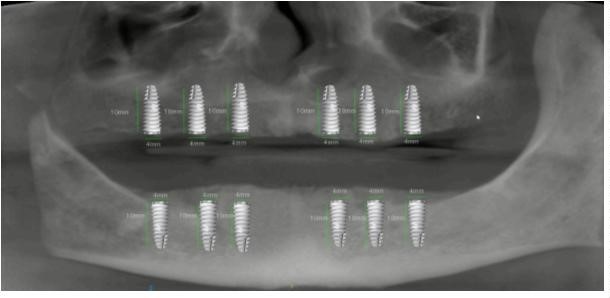

Para la planificación de la colocación de los implantes, la exploración clínica se complementa con la radiológica. La Radiografía Panorámica (OPG) (Figura 3) y la Tomografía Axial Computarizada (TAC) (Figura 4) nos permiten obtener la medición de los implantes y su punto de colocación.

Se comienza la intervención con la incisión lineal y despegamiento a espesor total en la maxilar. Los implantes planificados se colocan en 12, 14, 16, 22, 24, 26 según la secuencia de fresado del fabricante con irrigación constante con suero. Los implantes son RADHEX ®, de la línea PHIA, de titanio puro y conexión interna hexagonal.

Las referencias y medidas son las siguientes:

- 12, 14, 16, 22, 24, 26: 10 mm de longitud y 4 mm de diámetro. Una vez preparado el alveolo, se procede a la colocación de cada implante en la arcada superior a una velocidad de 25 rpm y un torque de 40 N/cm, con el apoyo del set de la caja quirúrgica utilizada. (Figura 6)

La preparación quirúrgica de la arcada inferior siguió el mismo protocolo. Se realiza la incisión lineal y despegamiento a espesor total en la mandíbula. Se realiza la secuencia de fresado para la colocación de implantes según el fabricante en 32, 34, 36, 42, 44, 46 de la misma marca y modelo que los superiores.

Las referencias y medidas son las siguientes:

- 32, 34, 36, 42, 44, 46: 10 mm de longitud y 4 mm de diámetro.